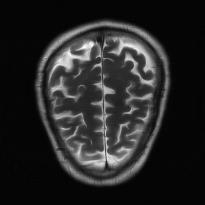

Recently, deep neural networks have greatly advanced undersampled Magnetic Resonance Image (MRI) reconstruction, wherein most studies follow the one-anatomy-one-network fashion, i.e., each expert network is trained and evaluated for a specific anatomy. Apart from inefficiency in training multiple independent models, such convention ignores the shared de-aliasing knowledge across various anatomies which can benefit each other. To explore the shared knowledge, one naive way is to combine all the data from various anatomies to train an all-round network. Unfortunately, despite the existence of the shared de-aliasing knowledge, we reveal that the exclusive knowledge across different anatomies can deteriorate specific reconstruction targets, yielding overall performance degradation. Observing this, in this study, we present a novel deep MRI reconstruction framework with both anatomy-shared and anatomy-specific parameterized learners, aiming to "seek common ground while reserving differences" across different anatomies.Particularly, the primary anatomy-shared learners are exposed to different anatomies to model flourishing shared knowledge, while the efficient anatomy-specific learners are trained with their target anatomy for exclusive knowledge. Four different implementations of anatomy-specific learners are presented and explored on the top of our framework in two MRI reconstruction networks. Comprehensive experiments on brain, knee and cardiac MRI datasets demonstrate that three of these learners are able to enhance reconstruction performance via multiple anatomy collaborative learning.

翻译:最近,深心神经网络大大推进了未经充分取样的磁共振成像(MRI)重建,其中大多数研究都遵循单一解剖一个网络的方式,即每个专家网络都经过特定解剖学的培训和评价。除了在培训多种独立模型方面效率低下之外,这种公约忽视了不同解剖学中共享的、可相互受益的解析知识。为了探索共享知识,一种天真的方法是将各解剖学家的所有数据结合起来,以训练一个全方位网络。不幸的是,尽管存在共享的解析知识,但我们发现,不同解剖学的独家知识可以恶化具体的重建目标,导致总体性能退化。在这项研究中,我们提出了一个新型的深度解剖重建框架,既有解剖学共享知识,又具有具体的解剖学参数,目的是“寻找共同的土壤,同时保留不同解剖学家之间的差异。此外,主要的解剖学学习者将接触不同的解剖学数据,通过多种解剖学重建的模型,并用不同的解剖学研究者将数据展示出一个全方位基础。